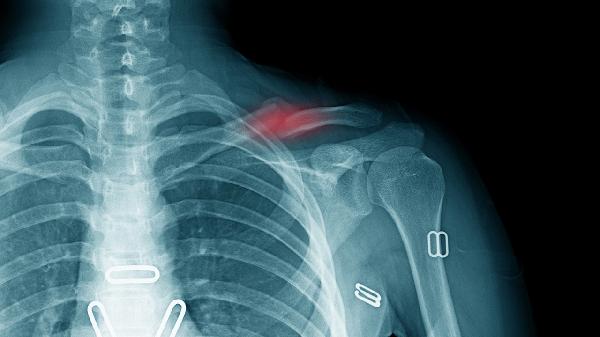

骨质欠规整是轻微骨折吗

骨质欠规整可能是轻微骨折的表现,也可能是其他骨骼异常情况。骨质欠规整通常需要通过影像学检查进一步明确诊断。 骨质欠规整在影像学上表现为骨皮质不连续或骨小梁排列紊乱,可能是由于轻微骨折导致。轻微骨折通

2025-11-10 04:58:00